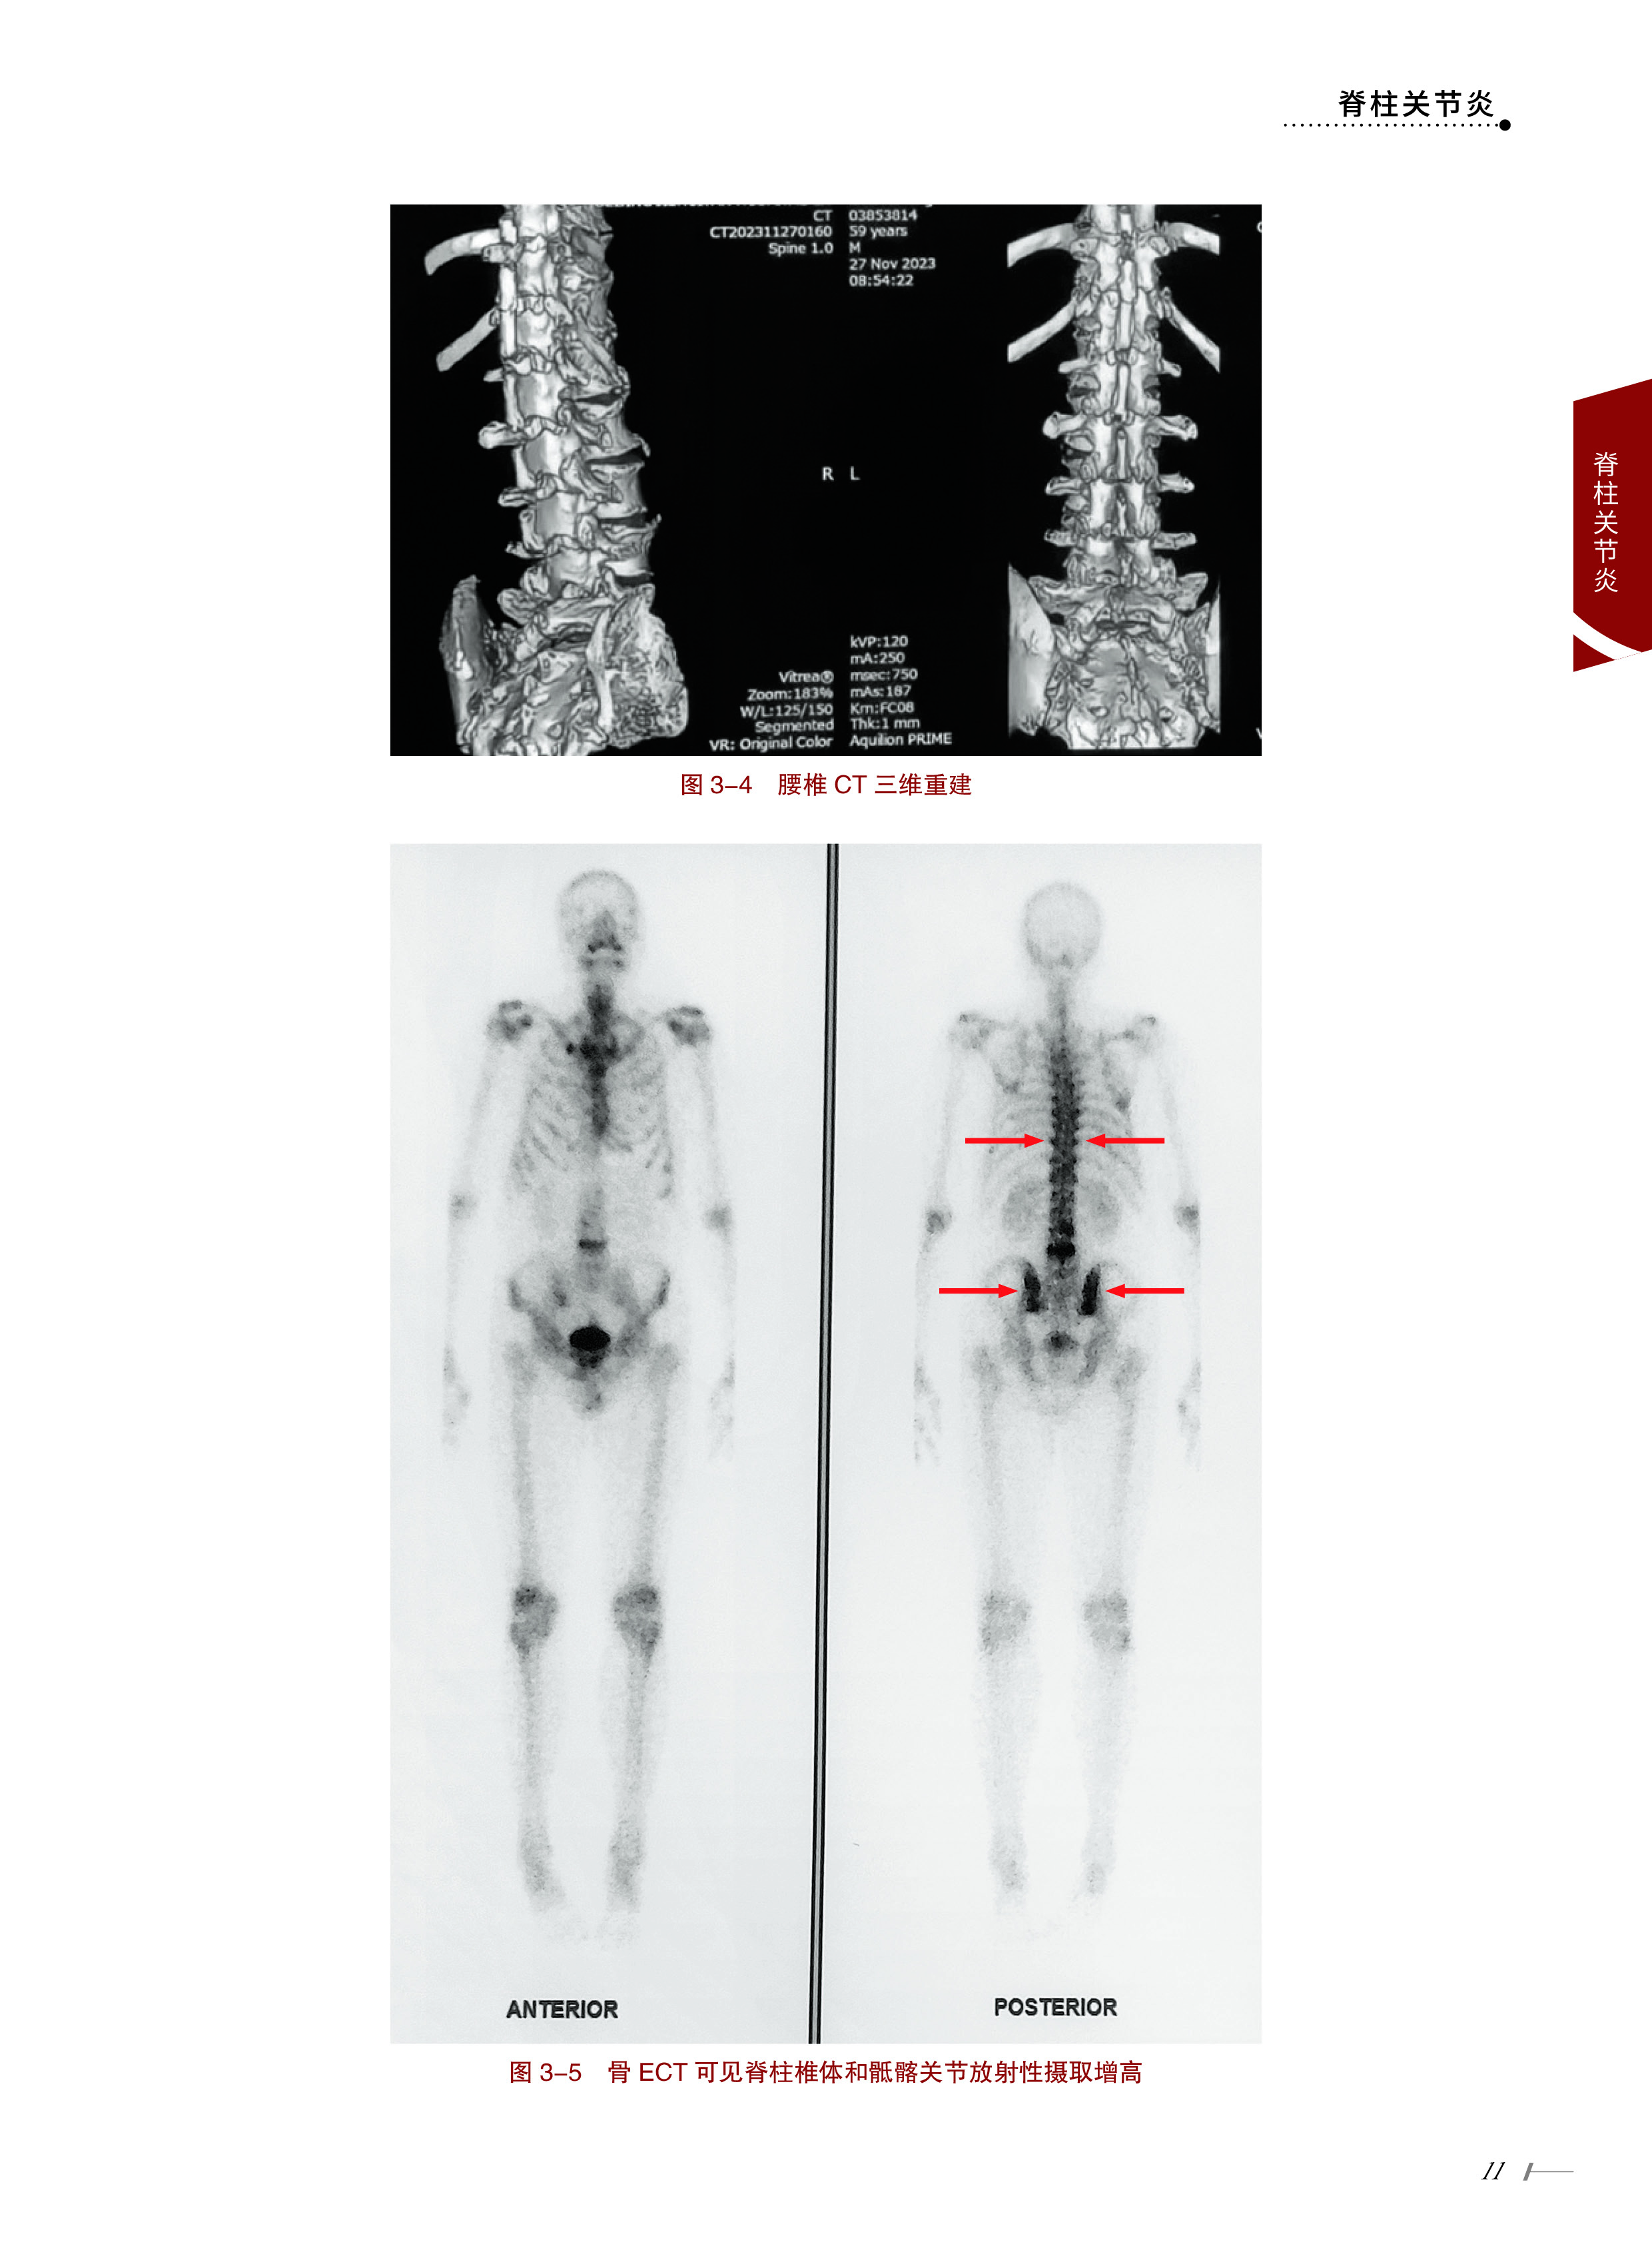

案例3 老年男性-慢性腰痛-虹膜炎 9